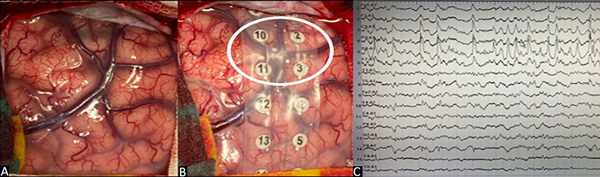

Mediante la apertura dural en H se identificó la presencia de cambios corticales a nivel frontopolar derecho. Se colocó grilla de 16 contactos en la circunvolución frontal superior y media derecha para control por EcoG con objetivación de descargas a nivel de los contactos 2-3-10 y 11 (Figura 3). Se realizó exéresis de la lesión con confirmación posterior, mediante el uso de EcoG, de la inexistencia de tejido residual epileptógeno (Figura 4).

Figura 3. Caso 1. A) Región dorso lateral frontal derecha precoronal. B) Grilla de 16 contactos. C) EcoG prerresección: patrón de ondas de alto voltaje, continuas, con una frecuencia mayor a 4 Hz sobre los canales que corresponden a los contactos 2-3-10-11.